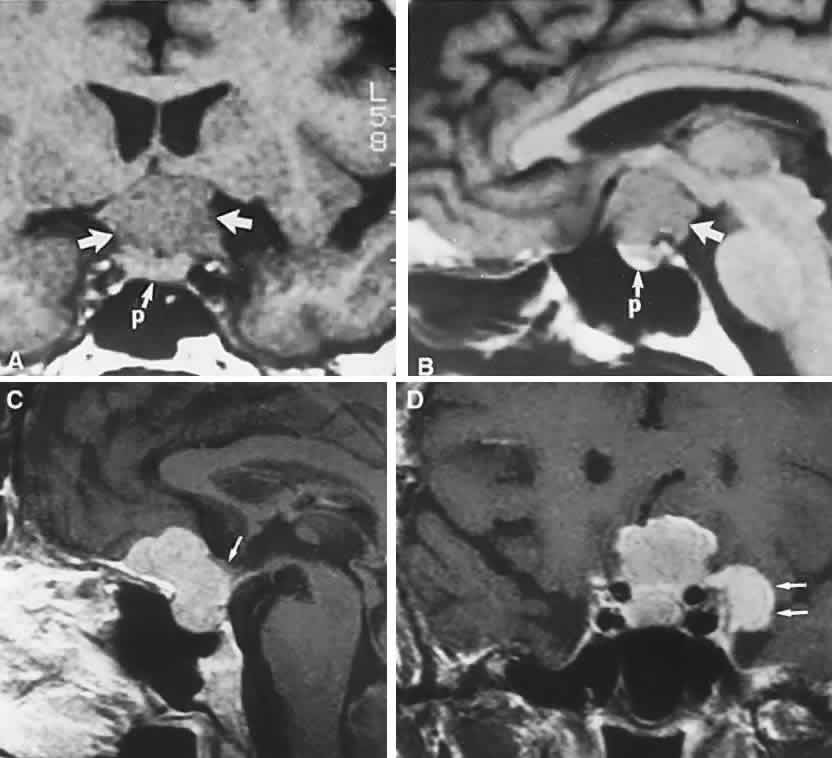

CT scanning retains special relevance to craniopharyngioma diagnosis, currently superior to MRI in detection of calcification and cyst formation (Fig. 7A to C); however, the extent of involvement of adjacent structures, that is, the optic chiasm, third ventricle, and intracavernous carotid artery, is more clearly delineated by MRI (Fig. 7D and E).93 Craniopharyngioma fluid collections are found to be uniformly bright on T2-weighted sequences, but on T1-weighted images, the signal intensity may range from hypointense to hyperintense, reflecting the heterogeneous contents of cysts. Because calcification and cyst formation are hallmarks of craniopharyngiomas, CT is more specific than MRI. At times, intrinsic infiltration of tumor may thicken the chiasm and contiguous optic nerve, a radiologic configuration that mimics glioma.94 Likewise, glioma may be simulated when the optic canal is invaded and enlarged, but accompanying bony erosion of the sella weighs heavily toward craniopharyngioma.

Fig. 7. Computed tomography scan of a large, multicystic craniopharyngioma. A. Axial section through the sella shows destruction of the bony skull base. Axial (B) and coronal (C) sections show cysts (white arrows) and calcification (arrowheads). Contrast-enhanced magnetic resonance imaging of the craniopharyngioma. Sagittal (D) and coronal (E) sections with gadolinium show solid and cystic (arrows) portions.